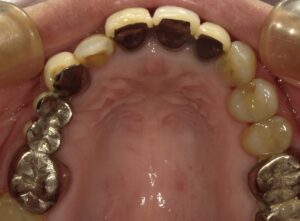

青○の部分が虫歯が進行して根っこだけになっています。

レントゲンでは青○の部分に嚢胞があります。